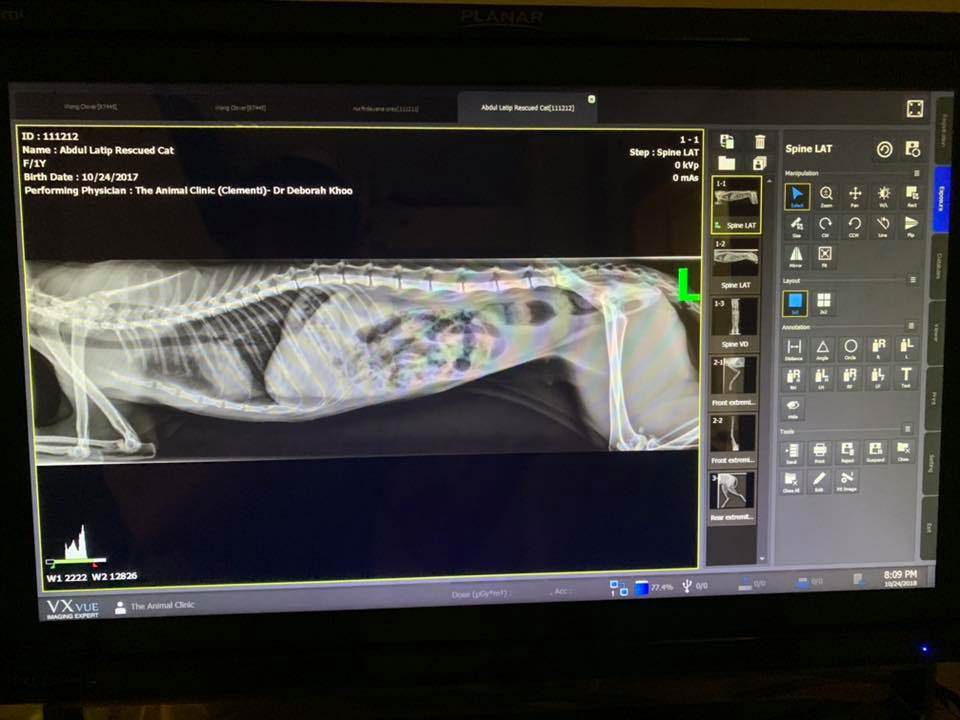

Masuri then took the kitten to a Clementi vet to examine her injuries.

Despite the fact that the X-ray did not reveal broken bones, the cat was unable to walk or stand. This was suspected to be the result of nerve damage by humans or homeless animals.

To regain her ability to walk, Cat may need therapy and acupuncture.

Her front left paw was completely unresponsive, according to a video published by Mr Masuri.